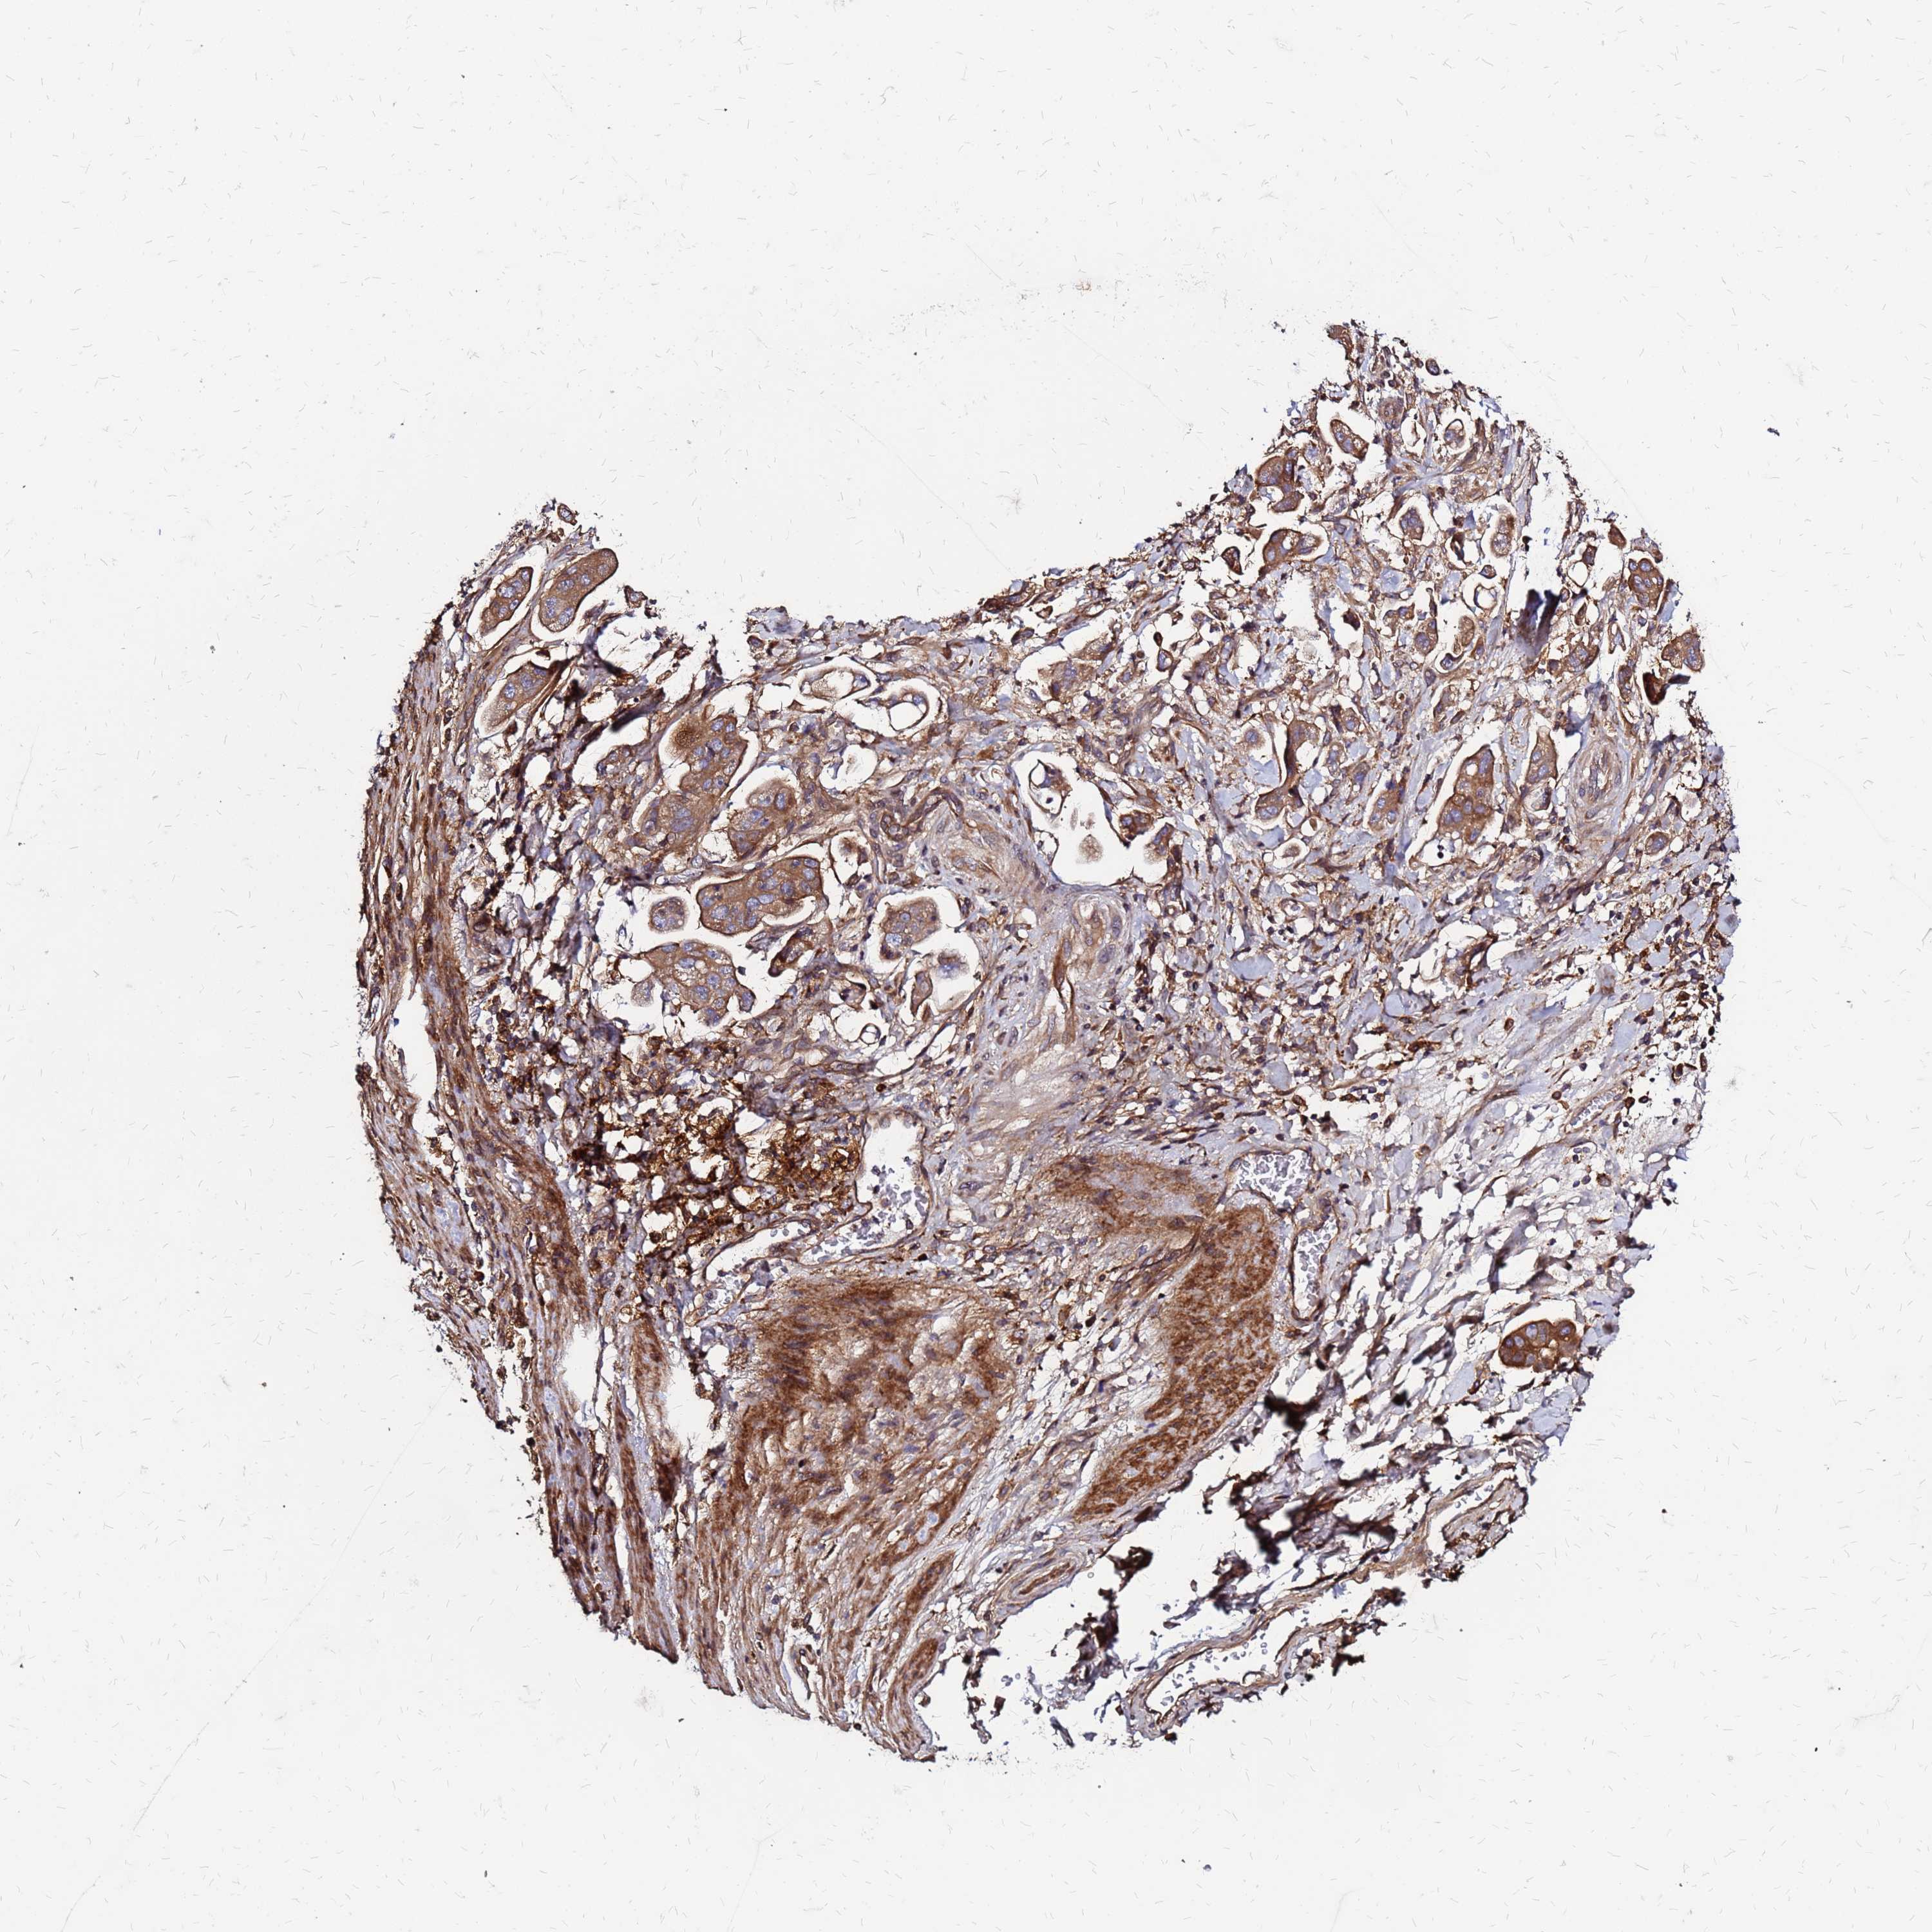

STOMACH CANCER - Protein expressioni

A mouse-over function shows sample information and annotation data. Click on an image to view it in a full screen mode. Samples can be filtered based on level of antibody staining by selecting one or several of the following categories: high, medium, low and not detected. The assay and annotation is described here.

Note that samples used for immunohistochemistry by the Human Protein Atlas do not correspond to samples in the TCGA dataset.

Antibody stainingi

Antibody staining in the annotated cell types in the current human tissue is reported as not detected, low, medium, or high, based on conventional immunohistochemistry profiling in selected tissues. This score is based on the combination of the staining intensity and fraction of stained cells.

Each image is clickable and will lead to virtual microscopy that enables deeper exploration of all samples and also displays staining intensity scores, fraction scores and subcellular localization as well as patient and tissue information for each sample.

Antibody HPA045696

Staining

High

Medium

Low

Not detected

Intensity

Strong

Moderate

Weak

Negative

Quantity

>75%

75%-25%

<25%

None

Location

Nuclear

Cytoplasmic/membranous

Cytoplasmic/membranous,nuclear

Adenocarcinoma, NOS